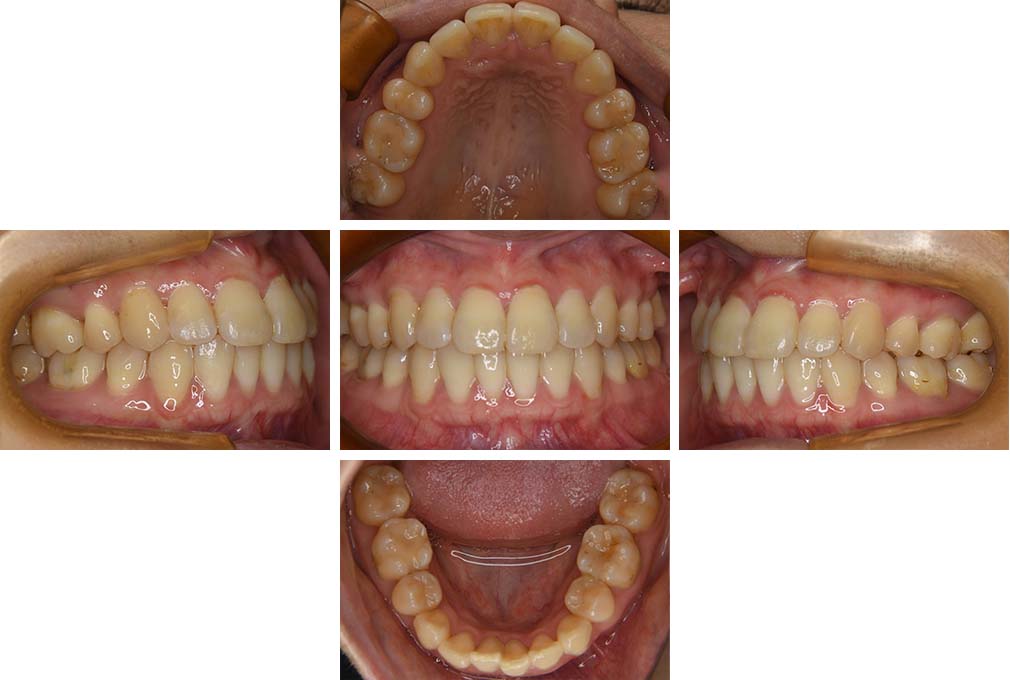

CASE:04

アングルⅢ級傾向を持つ叢生

初診時年齢 22歳

性別 女性

治療費の目安 105万円程度(治療開始時)

上顎右側犬歯が唇側に転位していることを主訴に県内歯科医院から紹介来院された。骨格的にはⅢ級傾向で上顎右側犬歯が唇側転位となり、側切歯が口蓋側に転位していた。下顎前歯が叢生になっていることも相まって上下の正中線は右側に大きくずれていた。アングルⅢ級傾向を持つ上下顎前歯部叢生と診断した。

上下顎小臼歯を抜歯していただき上顎舌側、下顎唇側マルチブラケット装置を使用して動的治療を行った。矯正用ゴムの使用など協力状態も良く、正中線の大きな移動があったのも関わらず2年10カ月で装置を撤去し保定へ移行した。保定移行後14年が経過し、ご息女の診察でご来院いただいていたことから、口腔内を拝見したが、下顎前歯のわずかなずれがあったものの大きな歯列の乱れはなく歯列は安定していた。動的治療期間2年10カ月間。

治療前

22歳6か月

治療後

動的治療期間2年10カ月間

25歳6か月

治療終了

動的治療終了後2年2カ月

28歳8か月

14年経過

動的治療終了後14年7カ月

40歳1か月